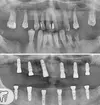

* Implantology and advanced surgical techniques in implantology.

* Peri-implantitis treatments